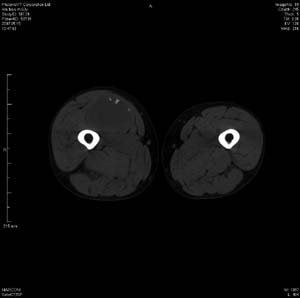

男 63岁 右大腿无痛性肿块11年,x片右大腿软组织肿块影,余无明显异常.ct值-13__239hu

右大腿股内侧股与收肌间隙间多发囊实性占位,界清.内示斑点状钙化.局部骨质无异常.肌肉推压移位表现.

考虑肌间隙病变.可有1,神经来源肿瘤.2,血管来源病变.3,淋巴来源肿瘤.4,脂肪来源肿瘤.5,滑膜来源肿瘤.结合病史只能考虑良性占位.建议增强或mri进一步分析.

同意,病史较长,病变周围分界清晰,考虑良性病变。病灶内有多发斑点状钙化,沿肌间隙生长,血管瘤或淋巴管瘤首先考虑。